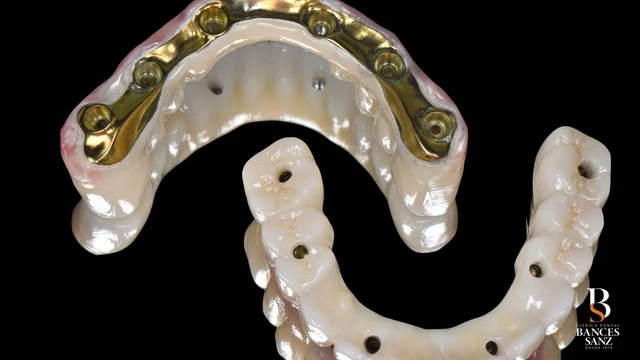

Se planificó una rehabilitación oral completa bimaxilar mediante la técnica All-on-6, colocando seis implantes en cada arcada, e integrando los implantes que sí podían mantenerse dentro del plan global.

- Colocar seis implantes estratégicamente distribuidos en cada arcada.

- Diseñar una prótesis fija completa soportada por esos implantes.

- Estructura de titanio.

- Recubrimiento de zirconio.